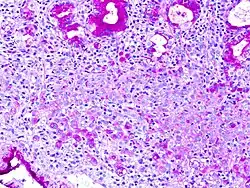

A coloração ácido periódico-Schiff ou coloração PAS (do inglês periodic acid–Schiff) é um método de coloração usado em histologia e patologia. Este método é primariamente usado para identificar glicogênio em tecidos. A reação do ácido periódico seletivamente oxida glicois vicinais, como encontrados na glicose, produzindo aldeídos, que ao reagirem com o reagente de Schiff produzem uma substância com cor púrpura-magenta.

A coloração PAS é principalmente usada para colorir estruturas contendo uma alta proporção de macromoléculas de carboidratos (glicogênio, glicoproteínas neutras), encontrados nos tecidos conjuntivos.